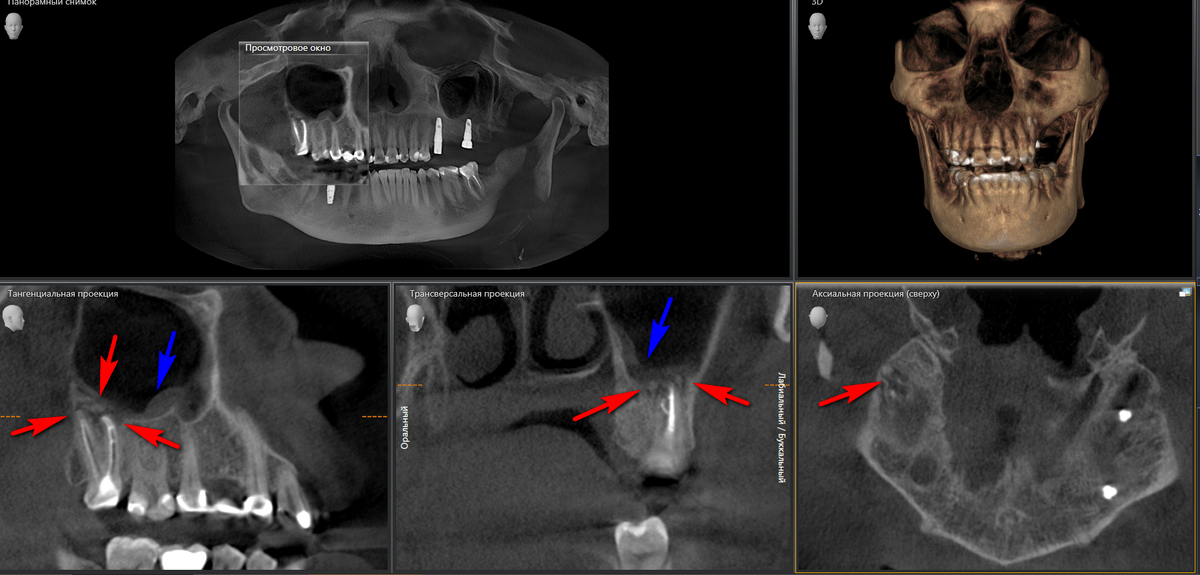

• Очаги хронической инфекции от зубов, чьи корни расположены либо в гайморовой пазухе, либо близко к ней - примерно 30%

• инфицированный пломбировочный материал/инструмент/корень зуба/имплантат, который попал в просвет верхнечелюстной пазухи (гайморовой пазухи) - в этом случае без помощи ЛОР-врача проблему решить скорее всего не получится;